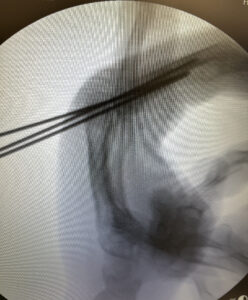

A técnica abaixo, utilizada em fraturas muito proximais de falange proximal na qual o fio de Kirschner é passado através da cabeça do metacarpo é conhecida como técnica de:

Qual é essa técnica?